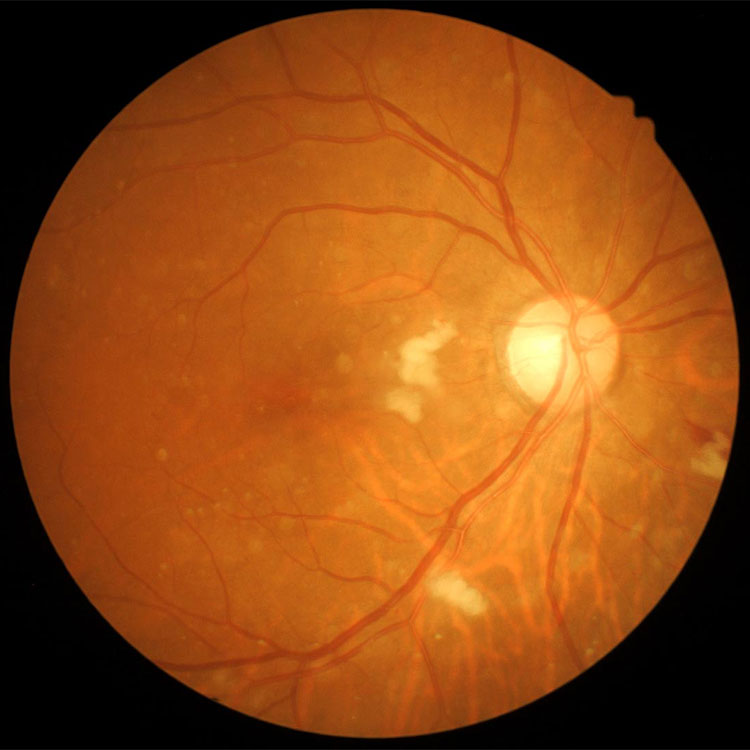

Атрофия зрительного нерва Лебера: Симптомы и лечение